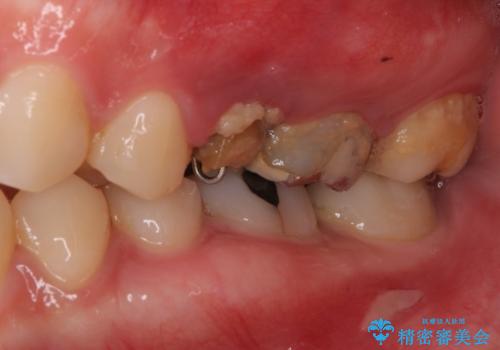

- 他院で大きな虫歯の歯を引っ張り出す治療中、あまりにも異臭がするとのことで来院された患者様です。

診査したところ、虫歯が広範囲で、粗造になった歯の表面に汚れがこびりついていました。また、歯根の半分以上の深さにまで亀裂が生じており、保存は不可能と診断しました。

抜歯後に治癒を待って、フルジルコニアブリッジにて補綴することとしました。